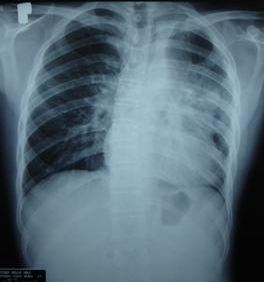

Tại đây các bác sỹ khám thấy bệnh nhân có khối u thành ngực trái kích thước 5x6cm, mật độ mềm, ranh giới không rõ. Tim bị đẩy sang phải (mỏm tim ở cạnh xương ức trái); hội chứng ba giảm toàn bộ phổi trái. Tinh hoàn hai bên đủ, không thấy tổn thương u.

Chụp CT: + Trên hình ảnh chụp CT lồng ngực: Vùng trung thất có khối lớn xâm lấn toàn bộ khoang ngực trái gây xẹp phổi trái, tổn thương lan rộng ra vùng thành ngực